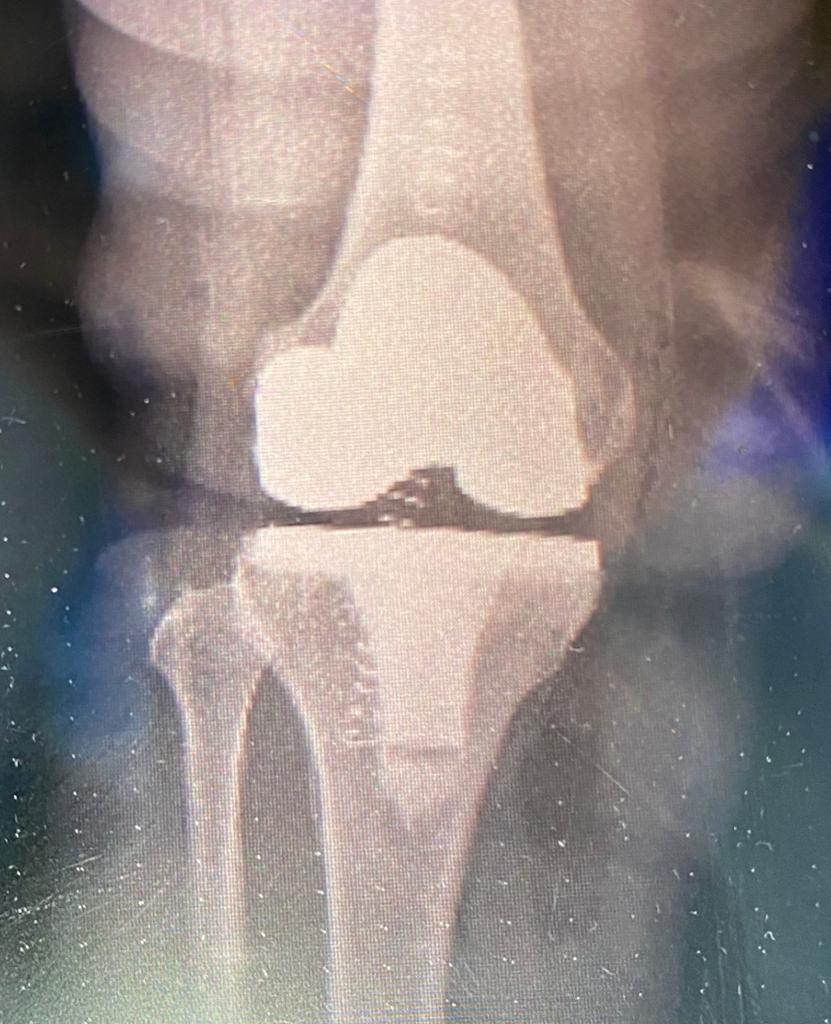

في إنجاز غير مسبوق على مستوى المستشفيات الطرفية ، نجح مستشفى الملك خالد في محافظة المجمعة في إجراء أول عملية إستبدال ركبة صناعية لسيدة كانت تعاني من مشكلة في الركبة وصعوبة في الحركة حيث إتضح بعد عمل الفحوصات والأشعة حاجتها لإجراء العملية، وقد تمكنت بفضل الله من المشي بعد العملية مباشرة وذلك بإشراف الفريق الجراحي وفريق العلاج الطبيعي، كما تم التأكد من سلامتها وعمل الفحوصات اللازمة والتأكد من السيطرة على الآلام وإعتمادها على نفسها في الحركة وأستطاعت الخروج بعد أقل ٤٨ ساعة من إجراء العملية وهي بصحة جيدة ولله الحمد .

تجدر الإشارة أن مستشفى الملك خالد في المجمعة قام بتأسيس برنامج جراحة إستبدال المفاصل الصناعية لمرضى خشونة مفصل الركبة وذلك نظراً للحاجة الماسة لمثل هذه الجراحات بسبب طول فترات الإنتظار في المستشفيات الرئيسة وتكبد عناء السفر بالنسبة للمرضى لإجراء هذه العمليات.

ويحتوي البرنامج على أحدث البروتوكلات في عمليات مفصل الركبة وإستخدم أحدث الطرق العلمية لإجراء العملية بواسطة الجراح المختص وذلك بإستخدام أكفأ أنواع المفاصل الصناعية، كما يتميز البرنامج بالإعتماد على التأهيل السريع و حركة المريض مباشرة بعد العملية وتقليل مدة التنويم إلى أقل من ٤٨ ساعة وضمان الحرص على سلامة المريض وإعتماد المريض على نفسه في الحركة قبل الخروج من المستشفى ، ويعتبر هذا البرنامج من أحدث البرامج لمثل هذه العمليات حيث يعتمد العمل على الفريق الواحد من أطباء التخدير و أخصائيي العمليات وفريق العلاج الطبيعي والتمريض والصيدلة.